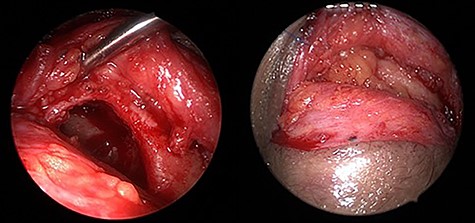

TOEA was selected after consulting the oculoplastic surgeon due to the lateral location of the frontal mucocele in addition to being an isolated mucocele with frontal sinus outflow obstruction. The frontal mucocele was successfully removed using TOEA through superior lid crease (SLC) incision followed by orbicularis oculi dissection, which exposed the orbital septum. The dissection until the superior orbital rim was exposed. The periosteum of the orbital rim was incised and peeled off, which exposed a bulging mass medially. The mass with surrounding fibrosis was excised completely and sent for histopathological evaluation. A bony defect was revealed at the lower aspect of the left frontal sinus measuring around 1.5 × 2.0 cm (Fig. 4). The left frontal sinus cavity was visualized completely through the bony defect using a combination of 0-degree and angled endoscopes. This revealed an isolated frontal sinus cavity with a completely obstructed frontal sinus drainage pathway medially, as a result of the previous head trauma sustained 40 years ago. Then, the frontal sinus mucosa was peeled off entirely from the bone using angled curettes followed by complete obliteration of the frontal sinus cavity using s fat graft harvested from a small incision on the left periumbilical area (Fig. 5). The periosteum of the orbital rim and the skin incision were closed using multiple 5-0 Vicryl and 6-0 Vicryl Rapide sutures, respectively. The patient made an uneventful postoperative recovery and was discharged on the following day of the surgery in a stable condition.

(a, b) Trans-orbital superior lid crease marking of the left eye and dissection until reaching the orbital rim. (c, d) A medial bulging mass was removed leaving a defect at lower aspect of left frontal sinus.